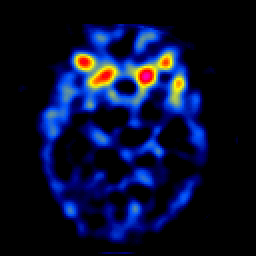

SPECT TL Study #4 -- Slice #22